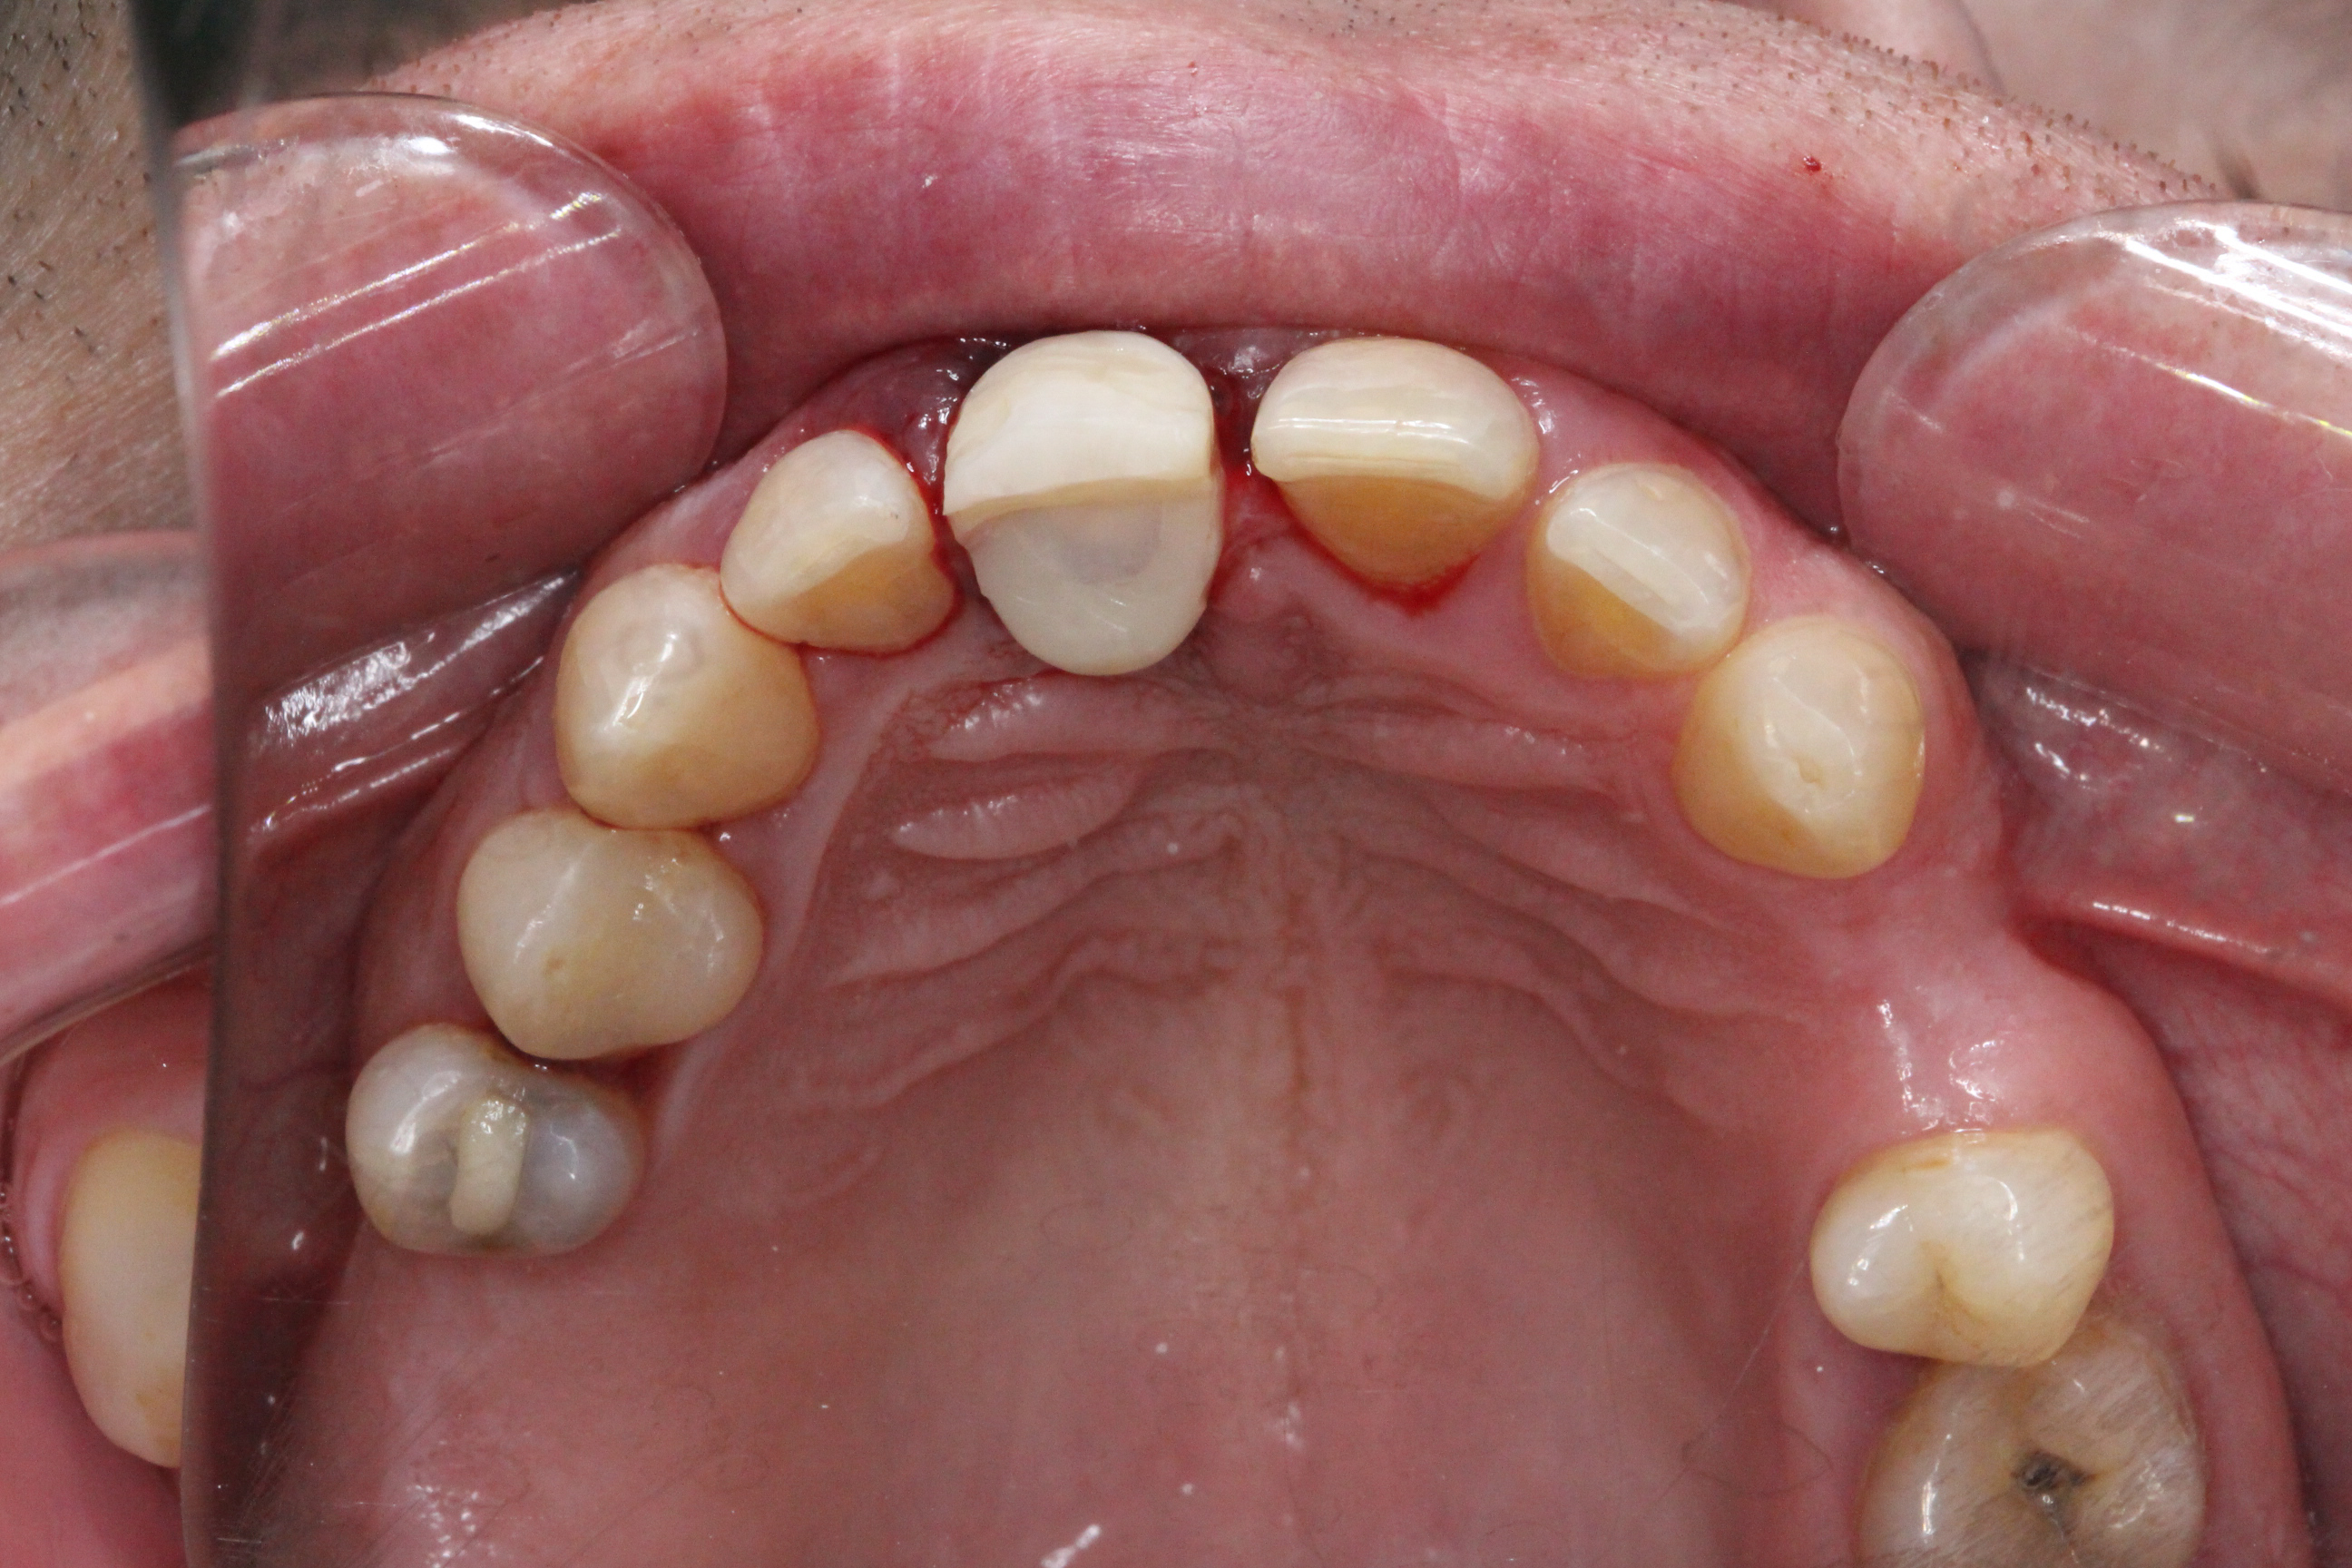

Medical history revealed that the patient was a non-smoker, had no diabetes, and no relevant systemic conditions. Dental history indicated previous trauma to tooth 21. Clinical examination showed Grade III mobility of tooth 21, localized severe periodontal destruction around the tooth, chronic periodontitis, bleeding on probing (BoP) of 10%, and the presence of calculus in the lower jaw. CBCT examination demonstrated complete buccal bone dehiscence around tooth 21 with limited remaining bone support. Therefore, extraction of tooth 21 was indicated.

Pre-operative planning was performed using the DICOMLAB digital planning platform. The workflow included a pre-operative CBCT scan of the upper jaw and a digitalintraoral scan.

An atraumatic extraction of tooth 21 was performed without flap elevation in order topreserve the soft tissue architecture.